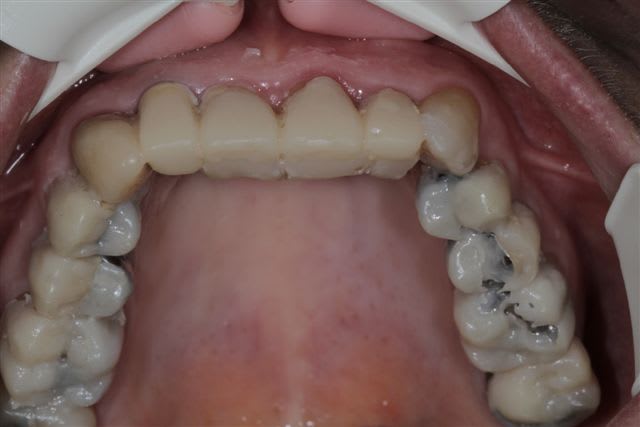

La suite, les soins ont commencés le 07/08.

Postérieur bas (16/08)et haut (14/09) en place, essayage des Emax avec "cutback".

Pour la teinte la patiente exige B1, sans maquillage, elle n'a pas attendu 47 ans pour que ça ne soit pas Blanc de blanc, alors là dessus j'ai cédé.

Cas typique de patient refusant l'ortho avant la réhabilitation global, avec un résultat esthétique ....disons que j'aime pas, bon si la patiente est contente!

Moi en tout cas au prochain patient qui refuse l'ortho nécessaire avant la réhabilitation globale, je lui montre ce cas. Merci encore je pense que cela sera utile.

Peut-on encore à ce stade diminuer (fortement) le volume des canines, réaligner les faces vestibulaires des PM droites, augmenter le volumes des centrales et distaliser les latérales???

Une petite élongation coronaire sur 11 et 21 n'aurait pas été de refus si racine pas trop courte.

Sinon a remarquer:

1) la patiente a une paralysie faciale (levre superieure gauche). Le fait que les canine-premolaires-molaires cote II soient plus longues que les incisives accentue ce probleme.

Je raccourcirais ttes les dents de 23 à 26 de 2mm.

2) Axe de 13 pas bon. trop de bombe vestibulaire. Peut etre que la dent n'est pas assez taillee. En tout cas je la trouve trop dominante dans le sourire.

09/10/2012 à 19h11

Les 2 canines sont effectivement très massives... Après tu fais avec les moyens que la patiente te donne, évidemment, mais là pour le coup je trouve pas ça très beau non plus.